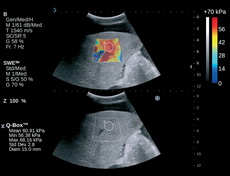

ShearWave Elastografie (SWE)